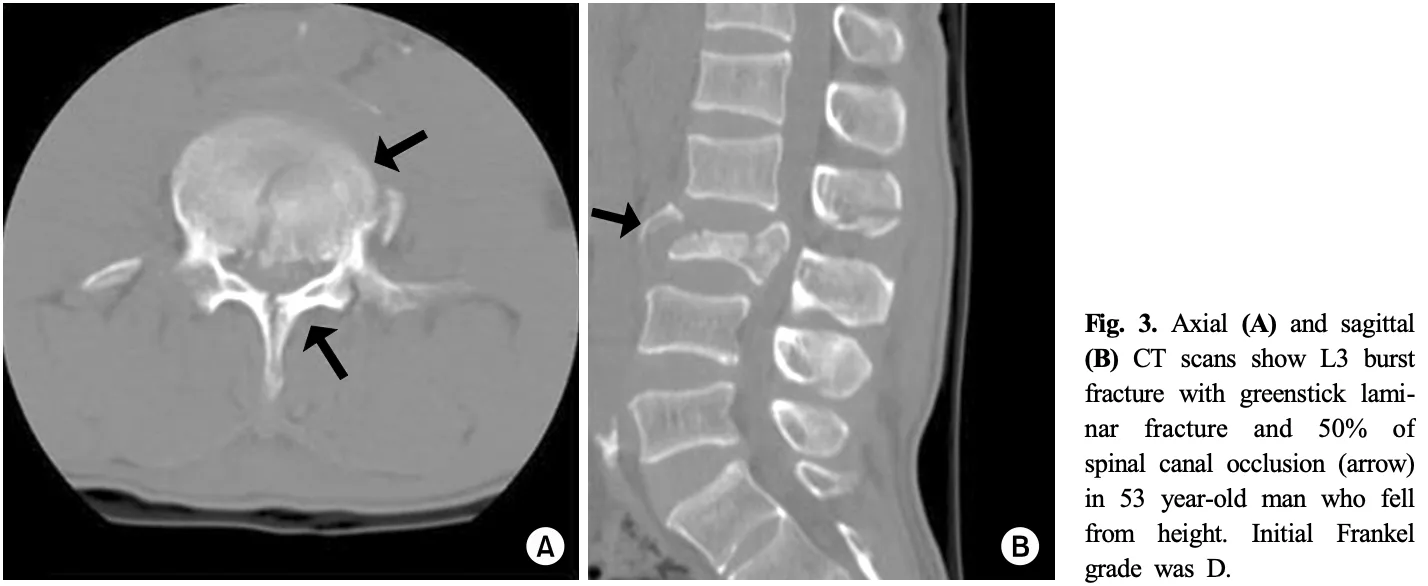

本日撮影したX線写真では, 椎体の高さが29 mmから24 mmと5 mmも短縮しており, また, 椎体後壁にも骨折が及んでいて, 破裂骨折と診断し, CTをオーダーしました.

骨片が脊柱管内に突出して, 脊柱管が狭くなっています.

また, 椎体後方の椎弓の骨折を合併しています.

その結果, 脊柱管内に骨片が突出していました.